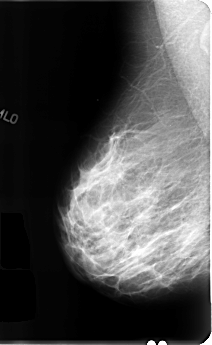

B_3111_1.RIGHT_MLO

RIGHT_CC LINES 4792 PIXELS_PER_LINE 2880 BITS_PER_PIXEL 12 RESOLUTION 50 NON_OVERLAY

RIGHT_MLO LINES 4824 PIXELS_PER_LINE 2960 BITS_PER_PIXEL 12 RESOLUTION 50 NON_OVERLAY